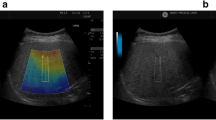

Vibration-controlled transient elastography (VCTE) commonly delivered by the FibroScan device (Echosens, Paris, France) measures the velocity of the shear wave that is converted to stiffness using the Young’s module [19]. It has been recognized as a rapid and non-invasive technique in the diagnosis and staging of liver fibrosis [20,21,22,23]. Controlled attenuation parameter (CAP) is a novel physical parameter based on the properties of ultrasonic signals acquired by the FbroScan [24]. CAP measures ultrasound attenuation at the central frequency of the VCTE at M or regular probe [25], but its accuracy may be affected by variations in cut-off values of different steatosis grades and different covariates [26].

Histopathological findings were reported as published, and the NAFLD activity score represents the sum of the scores for hepatic steatosis, lobular inflammation and hepatocyte ballooning [27]. Steatosis was graded according to the percent of the affected hepatocytes: mild (S1, 5–33%), moderate (S2, 34–66%), and severe (S3, ≥67%) [27]. The quality of the eligible studies, as assessed by the QUADAS-2 criteria, was independently appraised by two researchers (KP and SYB) (Fig. 2a and b). Two studies were assessed as “high risk” for index test and flow and timing in Risk of Bias. The remaining studies were estimated as “suboptimal” for unclear risk in the following domains: patient selection, index test, flow and timing. Most of the studies were identified as having low bias risk for patient selection and reference standard.